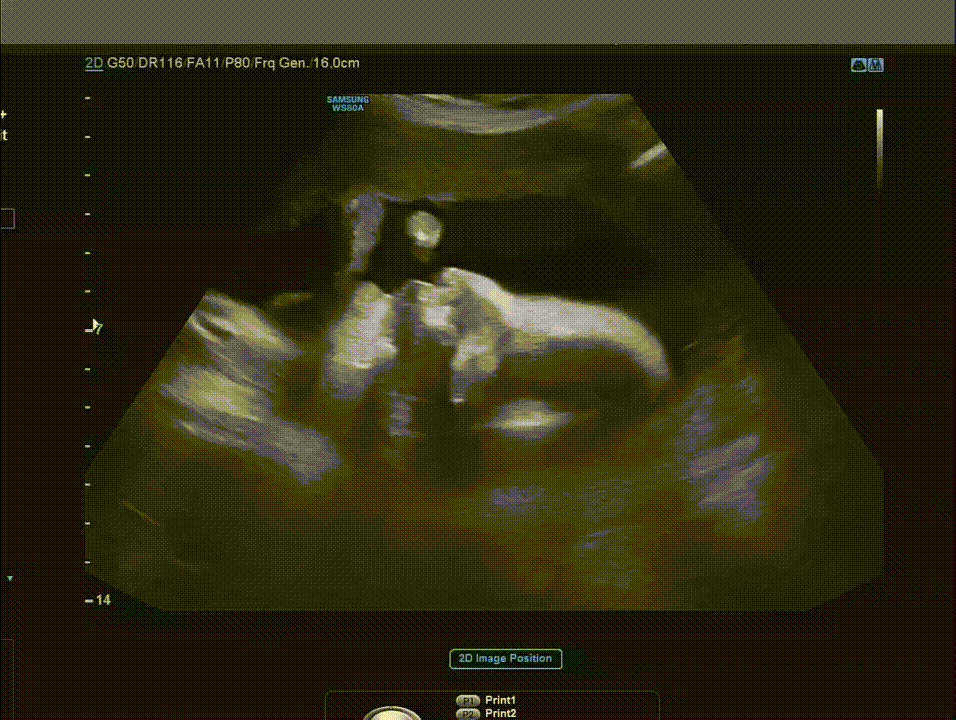

초음파를 살피던 의사의 말에 생각에 잠긴다. 그렇지. 나도 손가락 하나 움직이기 싫은 날이 많은데. 심장은 잘 뛰고 있으니 다행이라며 안심하는데, 모니터 속 손님이 입을 오물거린다.

“입은 움직이네요.”

마우스 커서를 입에 갖다 대며 의사도 모니터를 바라본다. 생긴 지 얼마 되지 않은 입술을 움직이며 손님이 뭐라고 말하고 있다. 쉬이. 배 속 양수 소리밖에 들리지 않지만, 입모양을 읽어보려 한다.

뭔가를 굉장히 말하고 싶은 입모양